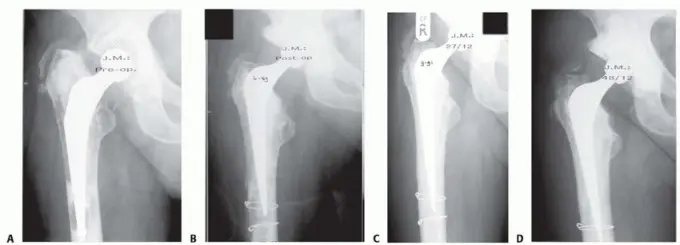

تعرف على تطعيم العظام بالضغط لعلاج فقدان عظم الفخذ في جراحات مراجعة الورك. الأستاذ الدكتور محمد هطيف يقدم الر…